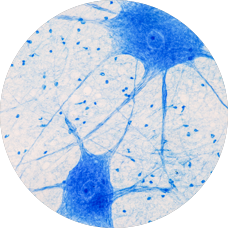

The initial analysis used age at death as a surrogate for age of onset. Prof. Vucic and his team hypothesized that it overestimated the number of steps required for onset, since death—by necessity—must come after onset. The researchers, therefore, re-analyzed the data by estimating the age of onset from a recently developed predictive model. As expected, the slope estimate was 5, indicating that 6 steps are required to trigger sporadic ALS. The 95% confidence intervals are highlighted in blue.

Adapted from Vucic S et al.4